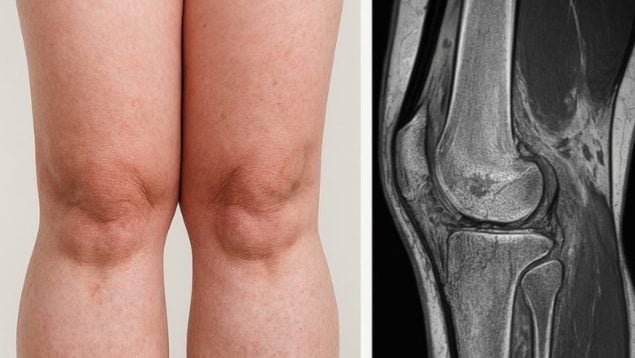

Pero, ¿qué es la lipedema? A diferencia del sobrepeso o la obesidad, el lipedema se caracteriza por una acumulación patológica de grasa en zonas específicas —piernas, caderas y brazos—, que no responde a dietas ni al ejercicio físico. Las pacientes suelen experimentar dolor espontáneo o al tacto, sensación de pesadez, tendencia a hematomas y una profunda carga emocional derivada de las alteraciones estéticas y funcionales.

Si no se trata a tiempo, el lipedema puede evolucionar hacia deformidades, sobrecarga articular y trastornos linfáticos que deterioran significativamente la calidad de vida.